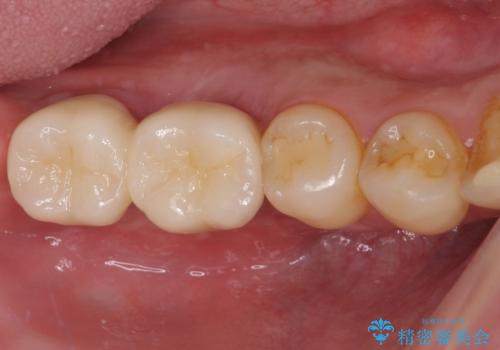

不適合ブリッジの除去 インプラントによる咬合再構成

奥歯の欠損 インプラントによる咬合機能回復

部分矯正を併用した奥歯のインプラント補綴治療

インビザライン矯正とインプラント補綴 深い咬み合わせと奥歯の欠損治療

歯周病にて保存不可能な歯をショートインプラントで回復する